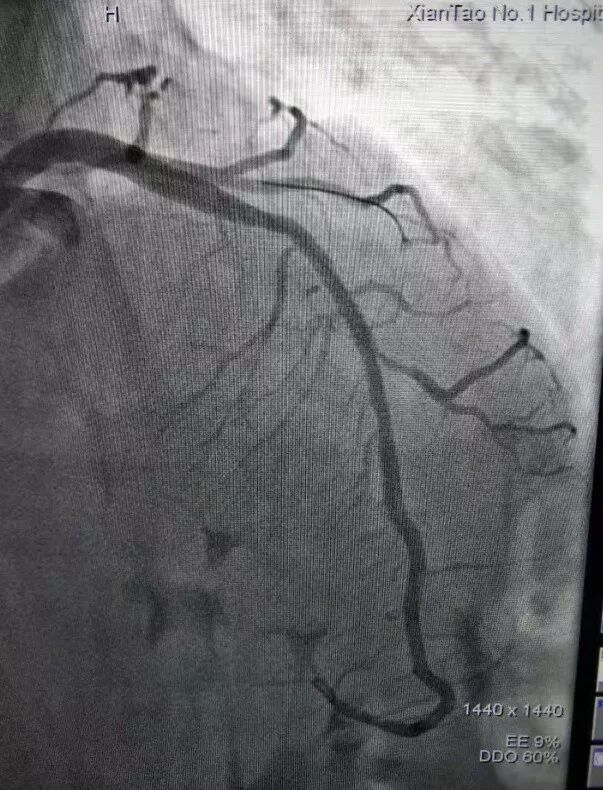

前降支中段次全闭塞并可见血栓影

患者达到心血管内科病房,复查心电图后,立即给予抗血小板、调脂、溶栓等治疗缓解症状。随后,进行介入手术。冠脉造影提示前降支中段有血栓,导致血管近乎闭塞,经过40分钟的手术,成功植入支架一枚,复查造影提示支架形态良好,血管畅通,患者转危为安。